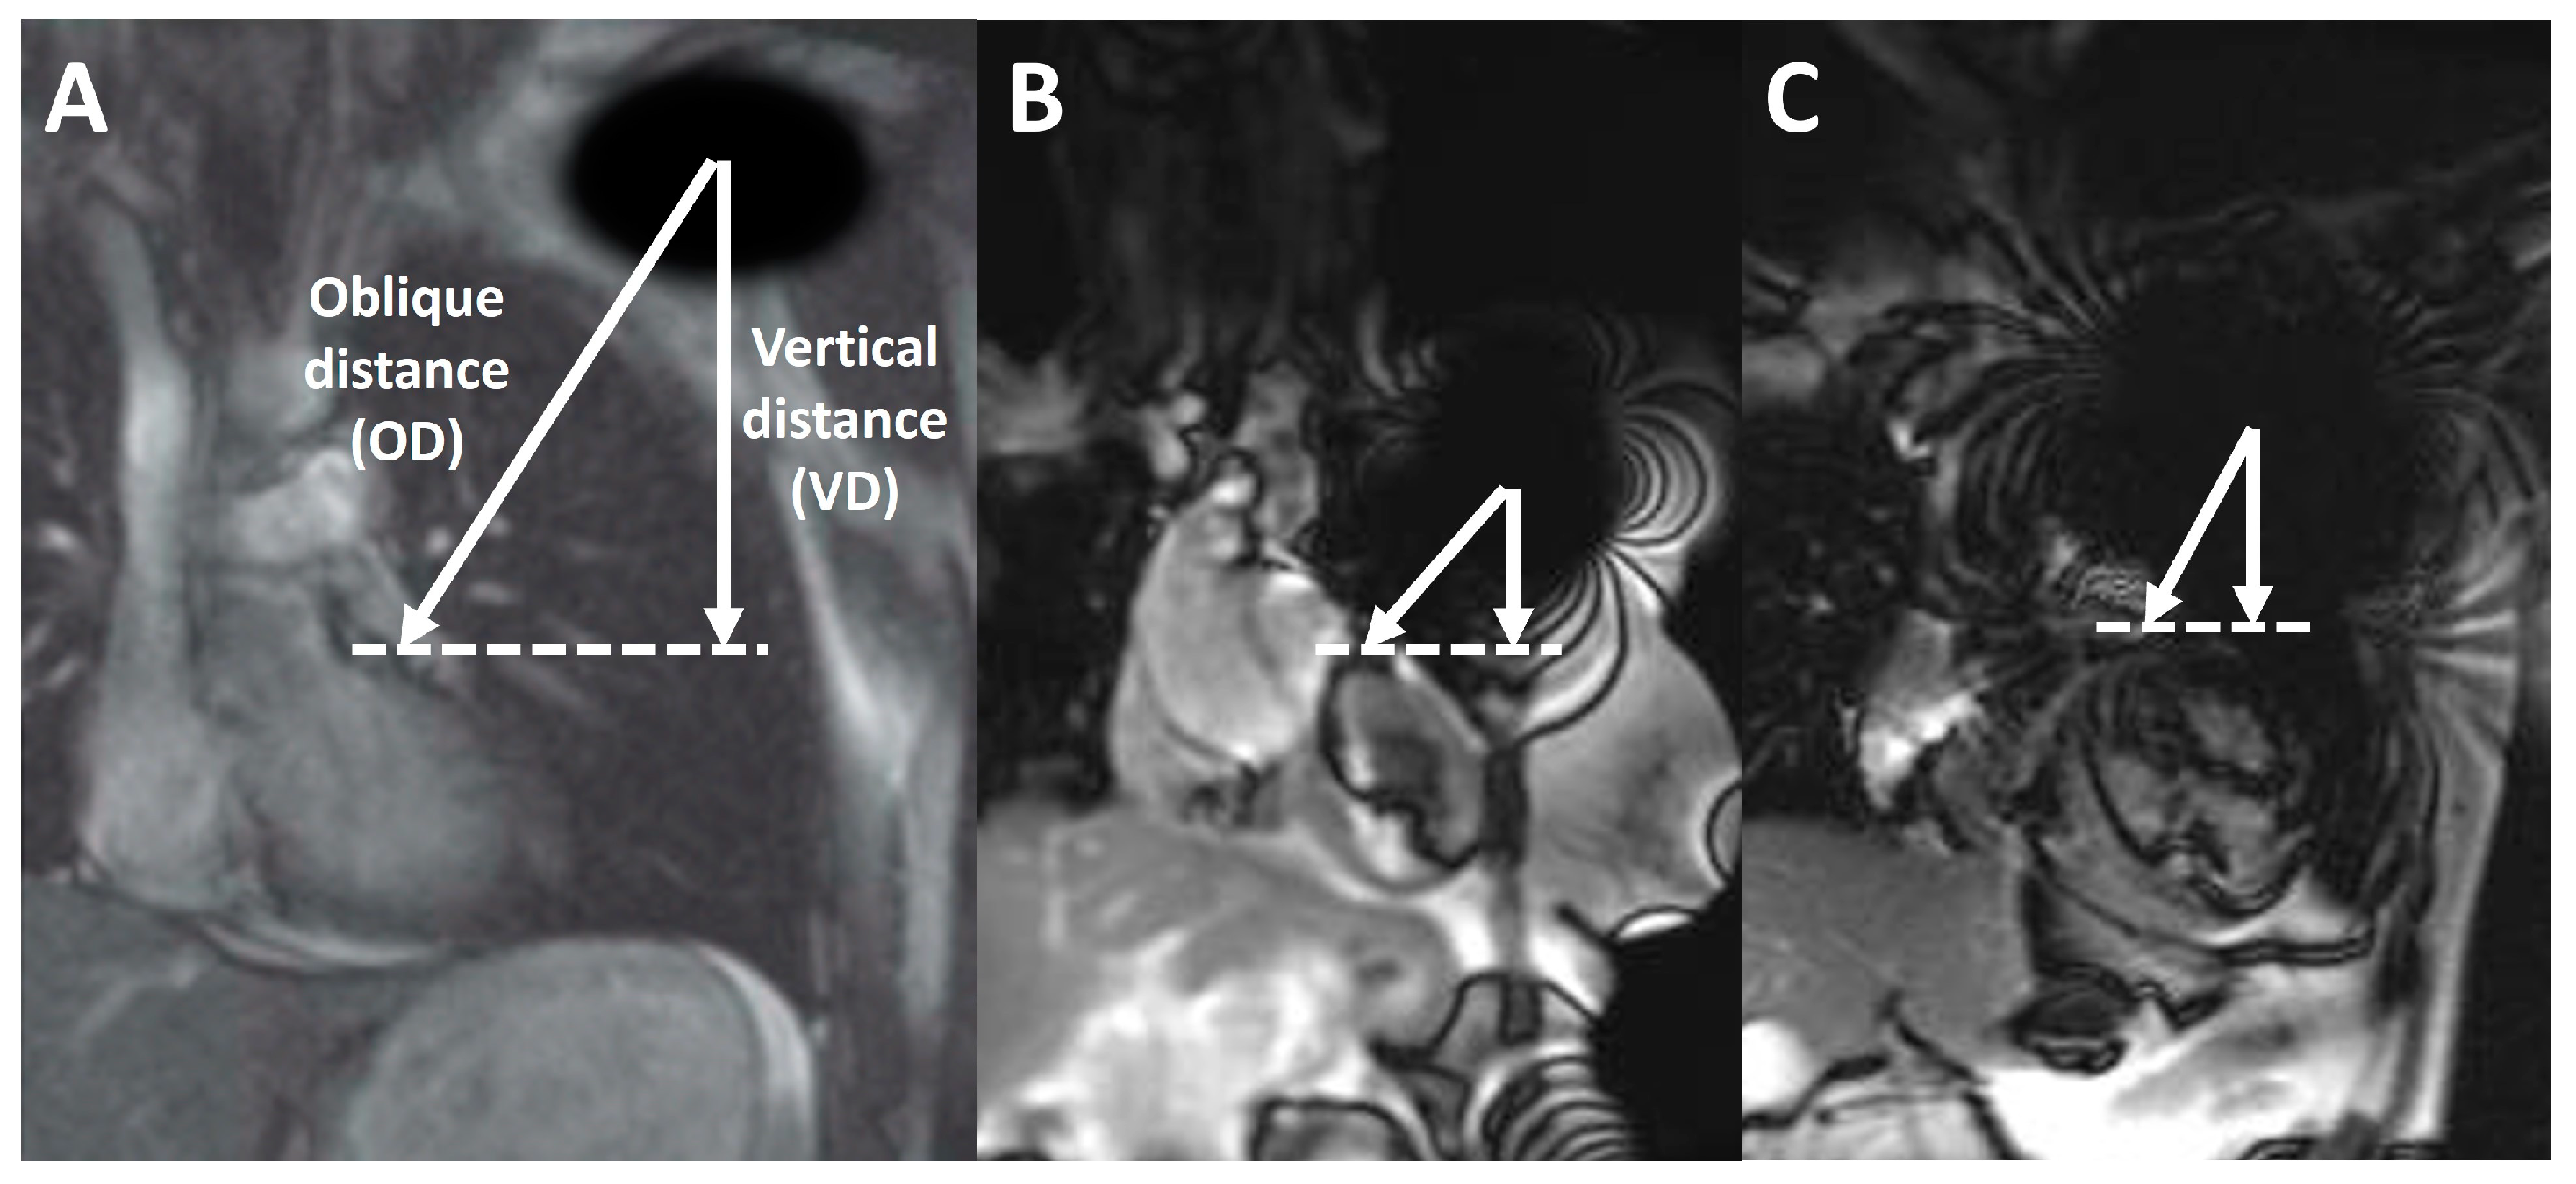

| Vertical distance, cm | 4.3 (1.6–6.2) | 5.5 (3.8–6.8) | 6.5 (3.1–8.0) | 7.5 (4.8–9.5) | <0.001 |

| Oblique distance, cm | 7.9 (6.6–8.7) | 9.2 (7.9–10.7) | 9.2 (8.4–10.8) | 9.3 (7.2–11.0) | 0.553 |